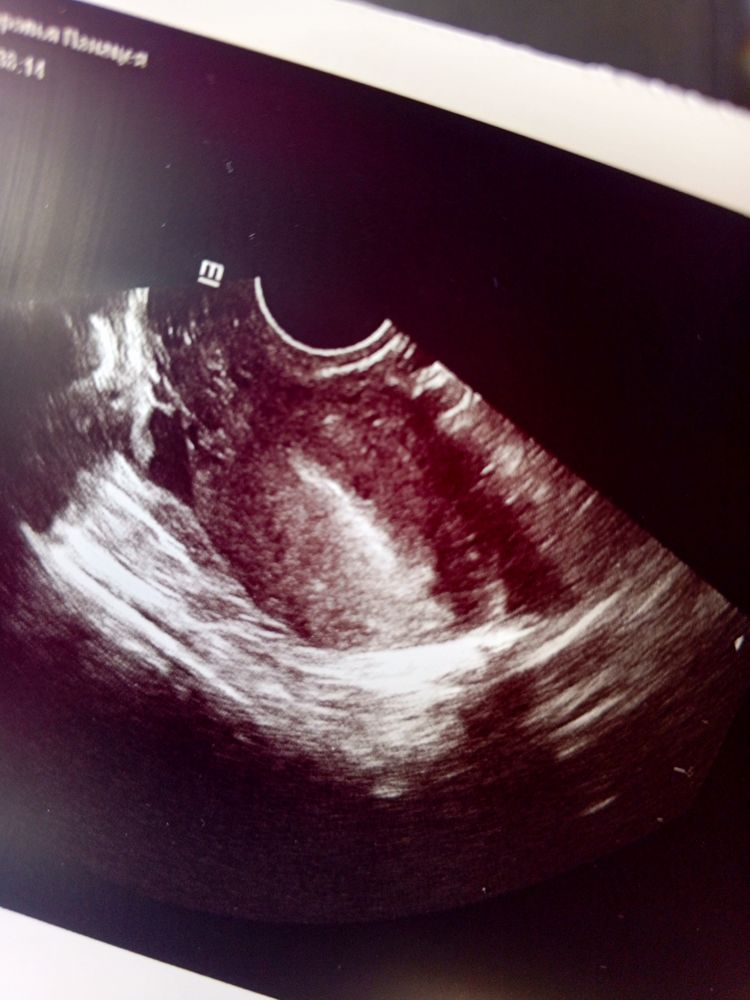

На УЗИ нашли яйцо но под вопросом?

Не похоже на плодное яйцо и ещё смущает что нет жёлтого тела,при беременности оно должно быть обязательно Это УЗИ чье ваше или вашей подруги,я запуталась уже,если это УЗИ с теми тестами что вы выкладывали без динамики,то по УЗИ 100% не пя,чтоб 2-3 мм пя разглядеть по УЗИ хгч должен быть выше 750,а с 750 тесты одинаковые,а с вашими там и 100 не будет

Жду чудо, незнаю,да что угодно,срез сосуда например,но это не пя,вам бы хгч в динамике сдать и прогестерон ещё,так как нет жёлтого тела

А что с хгч? Почему-то нет описания желтого тела в яичнике. Достоверно вообще не вижу ПЯ…

Жду чудо, так у меня при внематочной ничего не увеличено было,темболие при низком хгч,чему там увеличиваться,если там плодное яйцо меньше 1 мм при маленьком хгч,какие симптомы? Жидкость за маткой это не симптом беременности и темболие маточной,жёлтое тело не указано,пя под вопросом, вообще ничего не указывает на беременность маточную Так а что у вас с хгч,вы сдавали динамику?

Похоже на Б 🙏🙏🙏

Жду чудо, жёлтого тела нет? Какая беременность то?

Евгения, так жёлтое тело после овуляции образуется и если беременность не наступила,то оно угасает и приходят месячные,если наступила оно наооброт прогрессирует,без жёлтого тела беременность невозможна,или она уже тогда сорвалась и остатки какие-то тесты показывают

Не могу особо понять , но вроде похоже . Пусть будет оно и закончиться благополучной Б🙏

Похоже конечно! Это оно и есть 🤍🫶🏻

Эндометрий 23 УЗИ, фолликулометрия, много жидкости